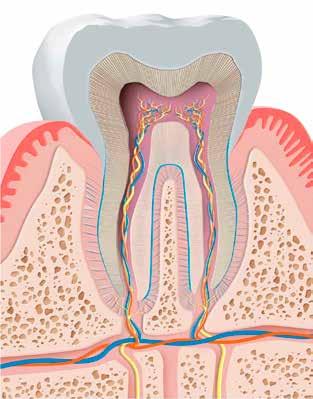

A klinikai vizsgálat során az UR1 reagál a viabilitási tesztre, és az ugyanazon a napon készült röntgenfelvételen nem mutat periapikális elváltozásokat (1. ábra).

Az UR1 elszíneződött, és palatálisabb helyzetben van, mint az ellenoldali központi UL1 (2. ábra)

Az esztétikai elemzés a gingivális zenit aszimmetriáját mutatja az UR1 és az UL1 között. Parodontális szonda segítségével, plexusérzéstelenítés után, az IA

típusú funkcionális hám megváltozott passzív erupcióját igazoljuk Coslet és mtsai. osztályozása szerint (3. ábra)

A lehető legkonzervatívabb helyreállító kezelés elvégzése érdekében a páciensnél, figyelembe véve a megtartott fogelem korát és vitalitását, a tervezés és a diagnosztikai felviaszolás után a közvetlen kompozit-helyreállítás elvégzése mellett döntünk.